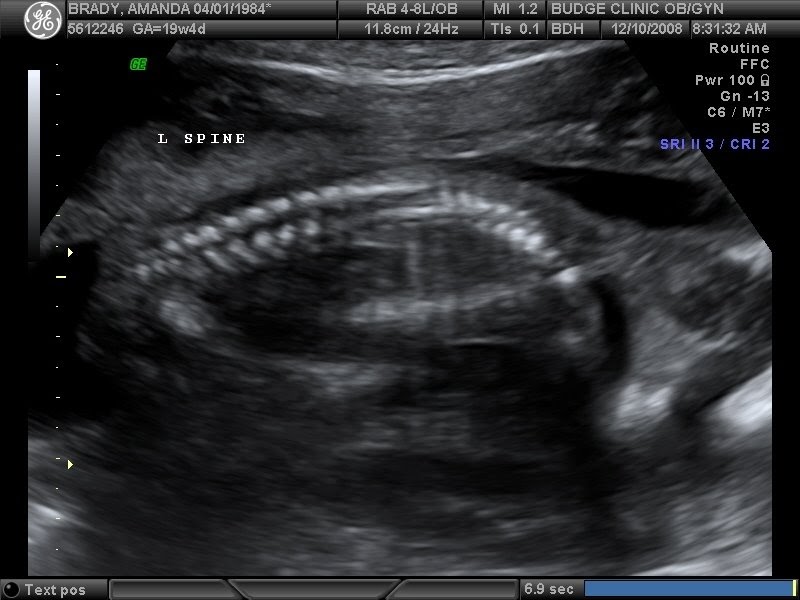

From brandonandamandabrady.blogspot.com

The Brady's Gastroschisis What Is Gastroschisis gastroschisis is a rare condition where your baby develops with a hole in their belly wall that allows their intestines and other organs to grow outside their body. gastroschisis is a condition where the intestines extend outside of the body through a hole beside the belly. gastroschisis is a paraumbilical abdominal wall defect associated with protrusion of. What Is Gastroschisis.